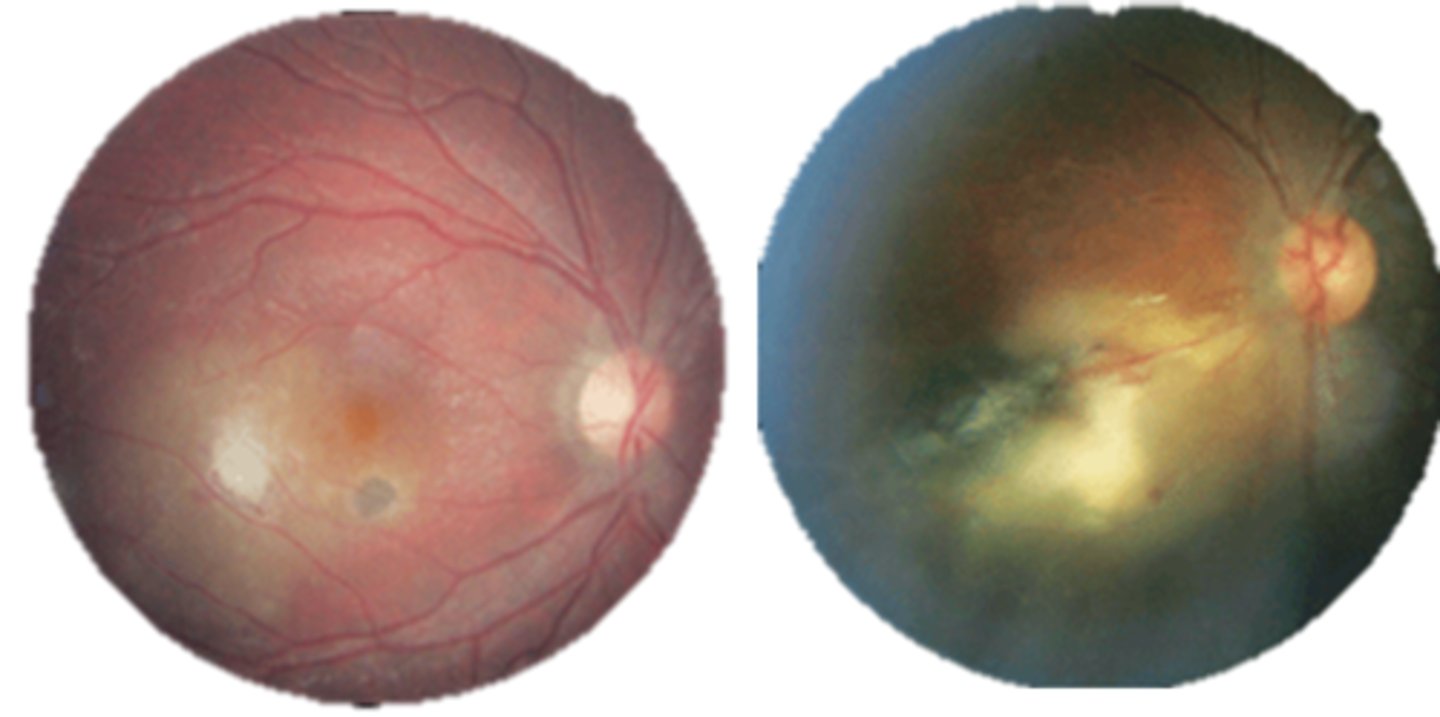

What findings of toxoplasmosis are seen here?

latent scars